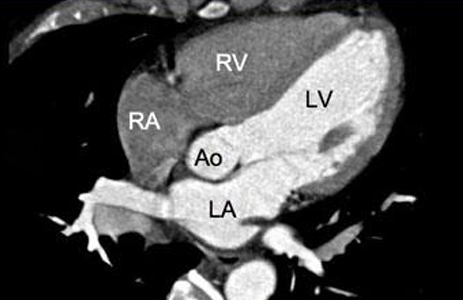

Cardiac CT Scan

Also known as Coronary CT Angiography (CCTA)

Coronary CT Angiography (CCTA)

Cardiac CT Scan (9)

4 chamber view

Cardiac MRI- Cardiac Axes

2 chamber view, 3 chamber view, 4 chamber view, 5 chamber view

Cardiac MRI- Cardiac Axes (4)

5 Chamber View